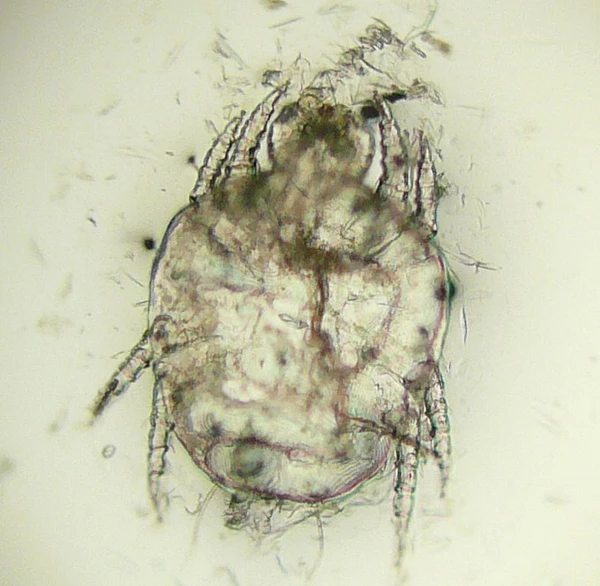

Возбудителем болезни являются клещи Cheyletiella yasguri (Smiley, 1965) и Cheyletiella blakei (Smiley, 1970), которые относятся к типу Arthropoda, кл. Arachnida, отр. Acariformes; п/отр. Trombidiformes, н/сем. Cheyletoidea, сем. Cheyletidae, роду Cheyletiella. Это мелкие клещи овальной формы. Взрослые клещи приблизительно 0.385 мм длиной. Гнатосома у них четко обособлена от тела, имеет вид конуса и плотные покровы. По бокам от неё располагаются крупные щупальца (пальпы) с 5 подвижно соединенными члениками, заканчивающимися когтевидными выростами. Две пары передних конечностей несколько удалены от двух пар задних. Лапки 1 пары ног не имеют коготков. На спинной стороне тела у самок один, а у самцов два гладких трапециевидных щита. Они слабо хитинизированы, желтовато-белого цвета. Краевые щетинки покрыты волосками. У самца половое отверстие расположено в задней половине на спинной стороне тела, а у самки открывается крупной продольной щелью на брюшной стороне.